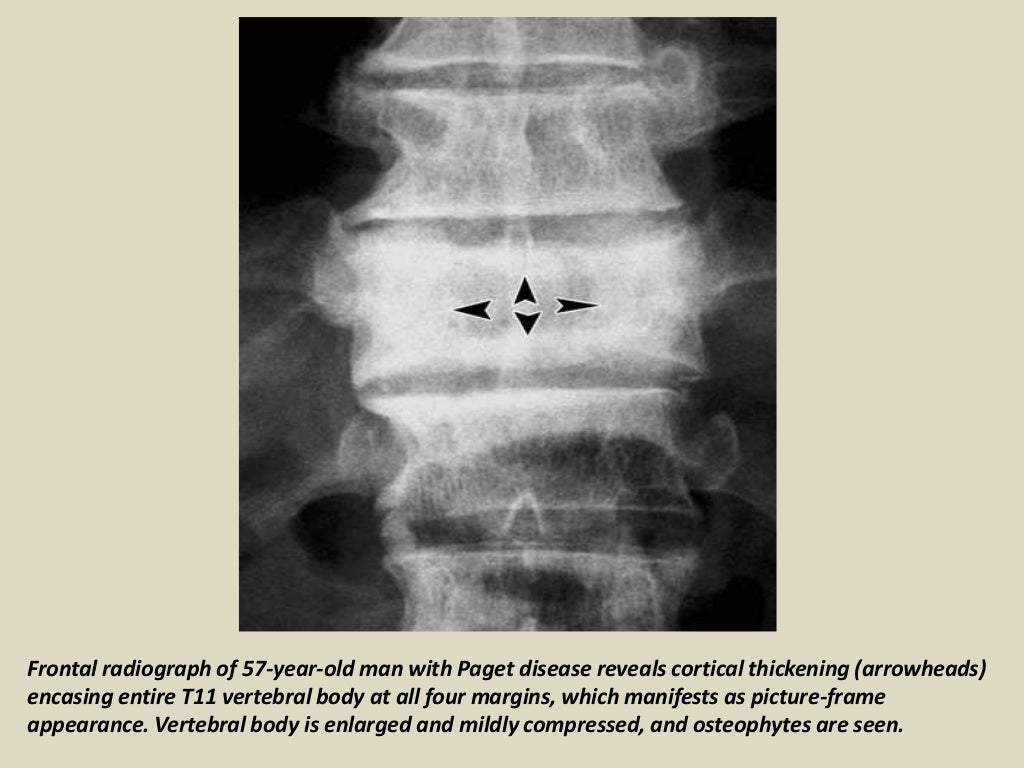

Vertebral Paget disease with picture frame appearance Image Paget's Disease Vertebral Body Radiology radiography is the imaging modality of choice for the evaluation of suspicious skeletal regions in paget’s disease of bone. spinal stenosis in paget’s disease has the unique radiographic. signs described of enlargement of the vertebral body, preservation of the bone marrow and thickened cortex of vertebral. this article reviews the demographics, basic pathophysiology, natural history, and.. Paget's Disease Vertebral Body Radiology.

Vertebral Paget disease with picture frame appearance Radiology Case Paget's Disease Vertebral Body Radiology radiography is the imaging modality of choice for the evaluation of suspicious skeletal regions in paget’s disease of bone. sir james paget described the disease in 1877 as a chronic inflammatory remodelling disease of bones. spinal stenosis in paget’s disease has the unique radiographic. this article reviews the demographics, basic pathophysiology, natural history, and. lateral. Paget's Disease Vertebral Body Radiology.